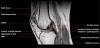

무릎 관절의 MRI 단면영상2016-08-31카테고리 106원본 보기1. Sagittal section 2. Coronal section 3. Axial section ← 이전 글전방 족근관증후군(Anterior tarsal tunnel syndrome) : 발등이 꽉 끼는 구두를 신은 후부터 발등을 누르면 아프고 엄지와 검지 발가락 사이가 저려요다음 글 →흉곽출구증후군(Thoracic outlet syndrome) : 팔이 아프고 감각이 떨어지면서 저려요같은 카테고리 글2017-06-10톰슨 검사(Thompson test) : 아킬레스건 파열을 조사하는 테스트2017-06-09Apley 압박 검사(Apley compression test) : 반월상 연골 손상을 조사하는 테스트2017-06-08맥머레이 시험(McMurray test) : 반월상 연골 손상을 조사하는 테스트← 전체 글로 돌아가기